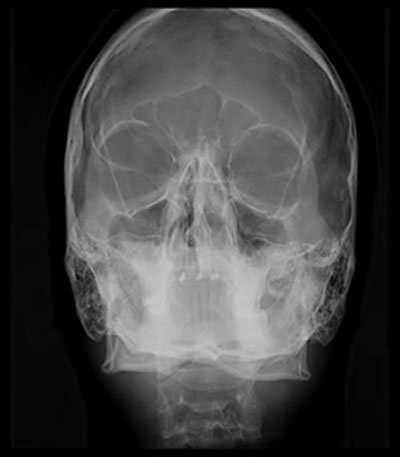

Póstero-Anterior (PA) Frontal ou Telerradiografia Frontal